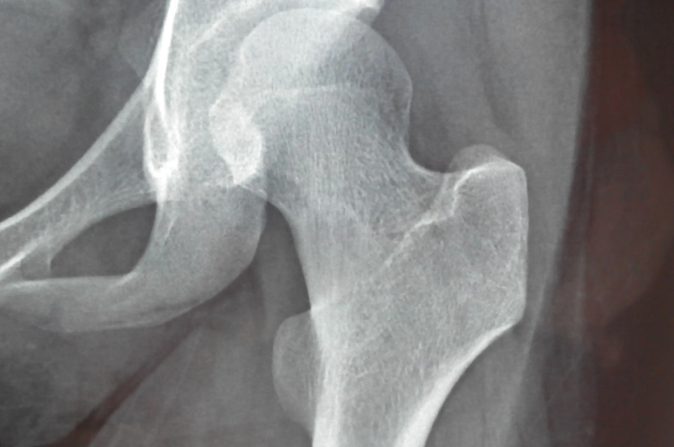

⑦ 고관절골절

고관절 통증 원인 - 왼쪽 고관절은 나이가 들어감에 따라 약해지고 부서지기 쉬우며 활동중에 금이 갈 수 있습니다. 이때 왼쪽 엉덩이와 사타구니에 집중된 통증 외에 왼쪽 엉덩이의 피부가 부어 오르거나 붉어지거나 멍이 드는 것을 볼 수 있습니다.